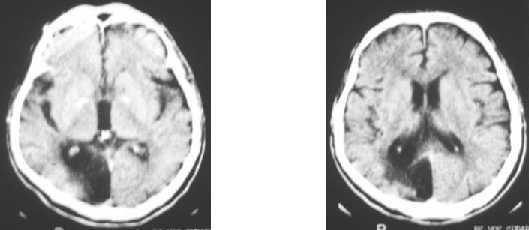

Ischemic brain diseases : infarct - PCA